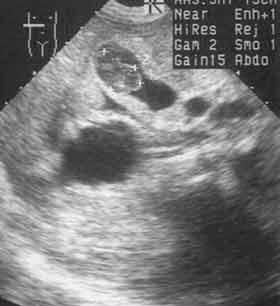

Ультразвуковое исследование в диагностике рака желудка.

Рис. 4. Метастаз рака желудка в желчном пузыре.

Новости лучевой диагностики 2001 1-2: 37-39